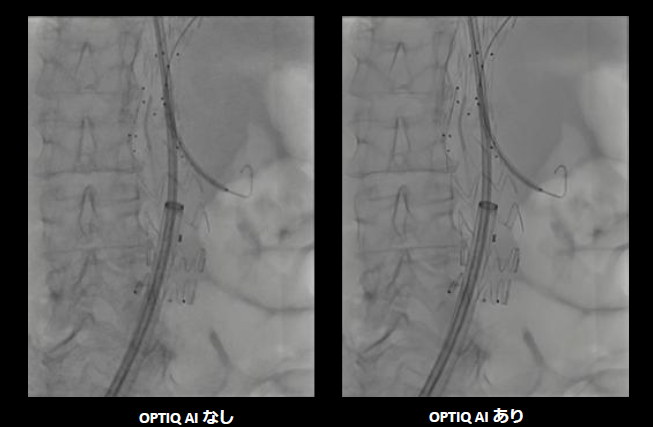

AIを用いた画像処理技術「OPTIQ AI」は、画像生成プロセスにおいてノイズを大幅に抑制し、高精細かつ高コントラストな画像を実現する。

CNR(コントラストノイズ比)をベースとした画像処理により、システム条件や患者さんの体格差、Cアームの角度などに影響を受けない、安定した画像を提供する。また、AIを活用した高度なアルゴリズムにより、幅広い2D透視・撮影モードおよびさまざまな部位において、信号強度を維持したまま量子ノイズおよび電子ノイズをリアルタイムで低減する。X線散乱や装置由来のノイズを抑制することで、微細な血管やカテーテル、ガイドワイヤーなどの治療デバイスを明瞭に描出し、良好な視認性を確保する。